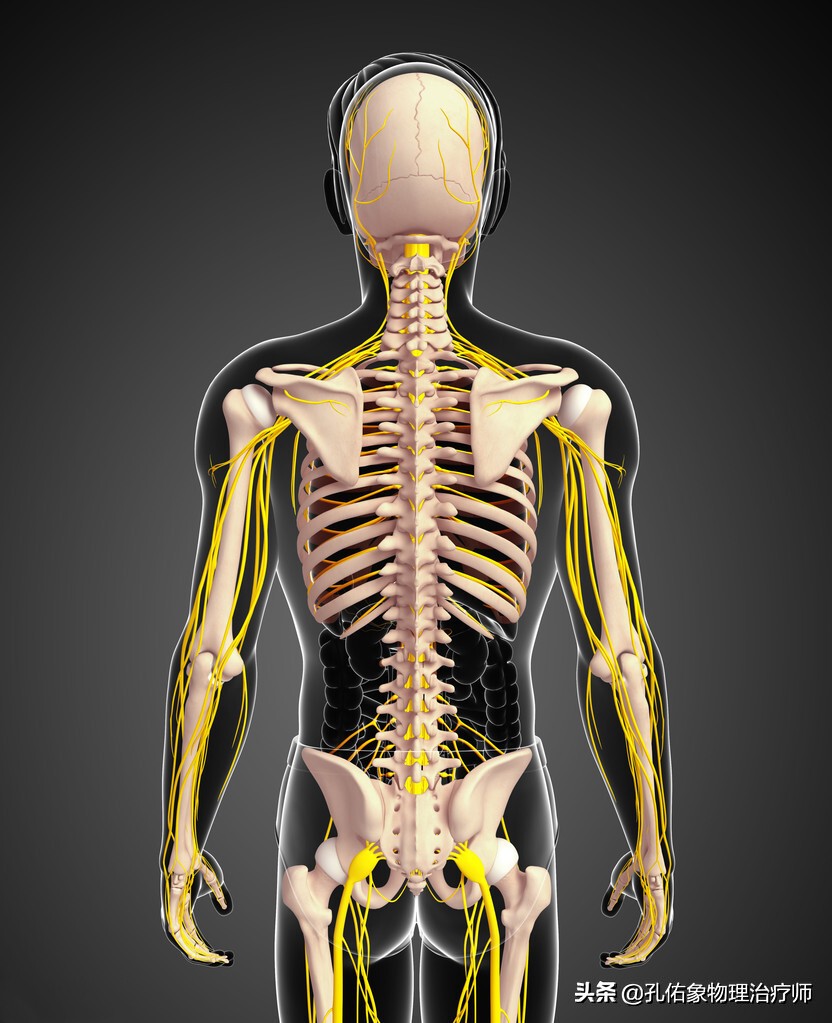

肩袖是长在肩关节周围的肌肉,如上图所示,如同肩的袖口一般,稳定和活动肩关节;若是在肩部撞击后,这些肌肉的肌腱就会被逐渐挤压、磨损而出现损伤;还有一些外伤也会引起。